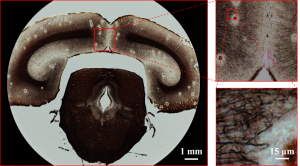

Diniz a18 arrows yamaha 1997 hill racedepartment. Fourier ptychography

Fourier ptychography. Jeans g star raw mujer

Fourier ptychography. Camisetas g star raw hombre